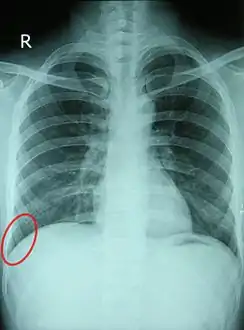

![]() أشعة سينية صدرية لرجل سليم في الثلاثين من عمره، وتظهر الردبة مُشاراً إليها بالأحمر. | |

يمكن عادةً رؤية كل زاوية من الزوايا الضلعية الحجابية على صورة الأشعة السينية على الصدر على أنها مسافة بادئة مدببة بحدة، حيث تميل إلى النزول (داكنة) بين كل نصف الحجاب الحاجز (أبيض) وجدار الصدر المجاور (أبيض). عادة ما يصل جزء صغير من كل رئة إلى الزاوية الضلعية الحجابية. تبلغ الزاوية الطبيعة عادةً ثلاثين درجة.

مع الانصباب الجنبي، غالبًا ما يتراكم السائل في الزاوية الضلعية الحجابية (بسبب الجاذبية). هذا يمكن أن يدفع الرئة لأعلى، مما يؤدي إلى "كسر حدة" الزاوية. الزاوية الخلفية هي الأعمق. ويدل تغير شكل الزاوية على وجود مرضٍ ما.

الأشعة السينية للصدر هي أول اختبار يتم إجراؤه للتأكد من وجود السائل الجنبي. يجب فحص الأشعة السينية الجانبية الوقوفية عند الاشتباه في حدوث انصباب جنبي. في الأشعة السينية الوقوفية، 75 مل من السوائل كافية لكسر حدة الزاوية الضلعية الحجابية الخلفية. عادة ما يتطلب تغير شكل الزاوية الجانبية حوالي 175 مل ولكن قد يستغرق ما يصل إلى 500 مل. الانصباب الجنبي الأكبر يعتم أجزاء من شق الصدر وقد يتسبب في انسحاب المنصف؛ إذا ما تجاوز الانصباب 4 ليتر قد يسبب عتامة كاملة في شق الصدر واندفاع المنصف إلى الجانب المقابل.[بحاجة لمصدر]